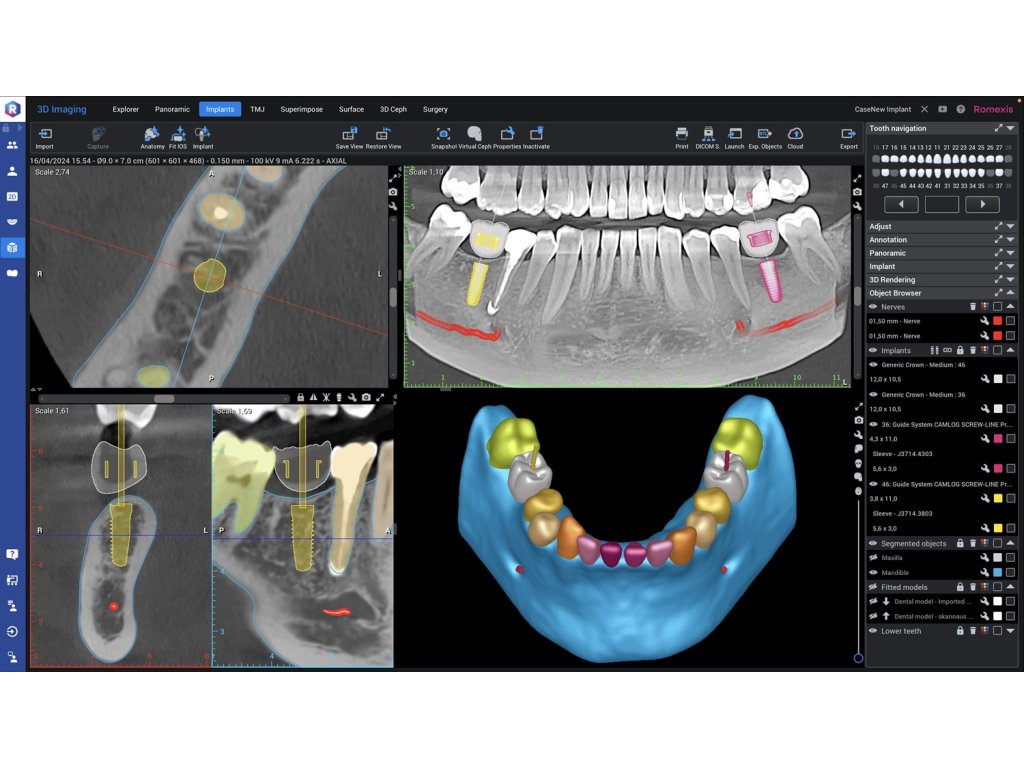

Výkonné diagnostické nástroje ve 3D - Univerzální diagnostické náhledy modulu Romexis 3D poskytují okamžitý přehled o anatomii pacienta – umožňují zobrazit snímky z různých projekcí nebo je automaticky převést na panoramatické snímky a řezy. Měřicí a značicí nástroje softwaru – jako je trasování nervového kanálu – dále podporují bezpečné a přesné plánování ošetření. Různé možnosti 3D zobrazení zlepšují vizualizaci a zároveň slouží jako skvělý nástroj pro edukaci pacientů.

Modul pro 3D zobrazování v softwaru Romexis lze plynule rozšířit na komplexní software pro plánování ošetření, který podporuje plánování implantátů i ortognátní chirurgie. Kompletní implantologický pracovní postup navíc umožňuje navrhovat chirurgické šablony pro zavádění implantátů a dlahy pro ortognátní operace.